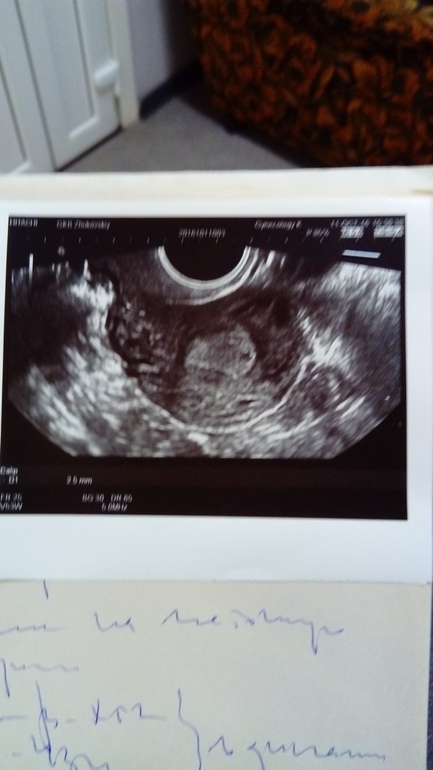

Через неделю на повторном узи увидели плодное яйцо без эмбриона, сказали что срок 3 недели, но срок очень разница с акушерским (акушерский 6-7недель)

У меня была задержка 8 дней пошла на узи , сказали все пусто ждите месячные. Через 2 дня месячных так и нет но с утра проснулась со странным чувствомв душе- сделала и тест и чуть с унитаза не упала еле еле бледная 2 полосочка. Разбудила мужа и рванула кровь сдавать срочно, после обеда результат хгч 175- беременность. еще через неделю снова иду на узи плодное яйцо в матке но эмбриона не видно,еще через неделю эмбрион появился но сербцебиения нет. Вообщем вероятно была поздняя овуляция или неизвестно что, но до сих пор разница по акушерским срокам и узи разбег 2 недели. Так что не переживайте просто надо подождать и все разовьется